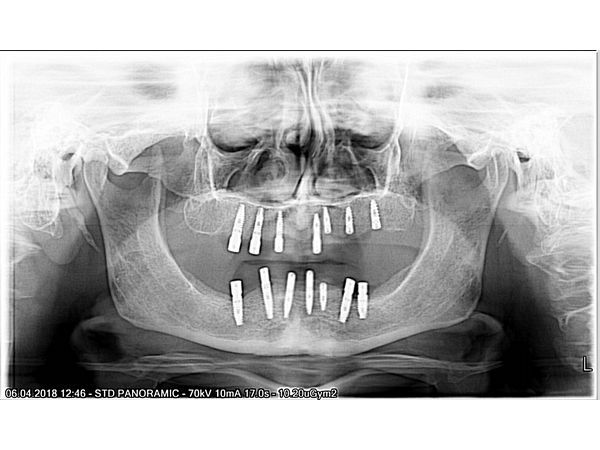

- После выполнения конусно-лучевой компьютерной томографии для планирования имплантации изготовлены навигационные шаблоны для установки имплантатов.

На первом хирургическом этапе была проведена дентальная имплантация на верхней челюсти и через несколько недель на нижней челюсти.

Через месяц установлены временные съёмные протезы. Через 4 месяца после приживления имплантатов выполнено протезирование несъёмными мостовидными протезами.